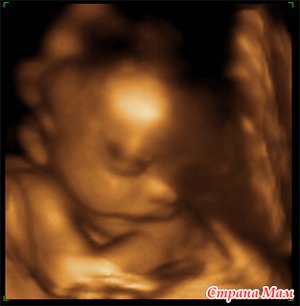

3Д-УЗИ дает возможность увидеть плод, части тельца и личико малыша, дает возможность записать видео, сделав таким образом видеоархив ребенка еще до его рождения.

Посмотрите разницу между "традициональными" УЗИ 2Д, 3Д и 4Д, картинки говорят сами за себя без слов.